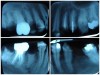

The patient in Figure 10 through Figure 12 was pregnant when she presented for dental treatment. The pregnancy was unplanned and she had had a lack of prenatal care. Continuing meth use during the pregnancy resulted in a positive toxic baby. She stated that she had just stopped using meth and had entered a rehabilitation facility a few days before. She was brought to the author’s clinic with a toothache. Note that as seen in these images, extreme accumulation of plaque, lack of oral hygiene, and severely decayed and missing teeth are classic manifestations in meth users.

Fig 10. Accumulation of soft plaque is typical of oral hygiene neglect associated with the use of methamphetamine.

Figure 10

Fig 11. Note demineralization of smooth surfaces, carious lesions at the gingival margins, and associated inflammation of the periodontium.

Figure 11

Fig 12. Radiographs of patient in Fig 10 and Fig 11 illustrating nonrestorability of the dentition.

Figure 12